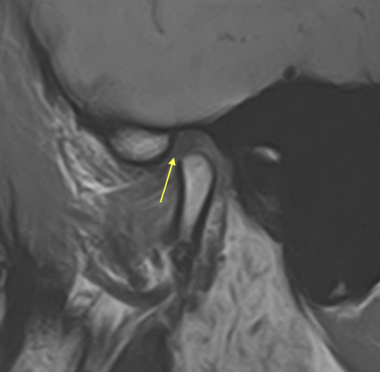

これは顎関節の MRI 画像です。歯科医院の矯正治療、また噛み合わせ治療で撮影することが一般的でないためご覧になったことが無い患者さんもいると思います。ただし顎関節の軟骨の状態を確認するためには MRI は必要なものです。皆さんも股関節、膝関節、肘関節で外傷や痛みがあったときに当然 MRI の精密検査があるはずです。こう考えると顎の「関節」の治療だけレントゲンや CT のみで済ませてしまう不誠実さを実感頂けると思います。

左側の顎関節画像の黄色い矢印は軟骨です。画像診断(読影)をすると顎関節に載っているはずの軟骨が前方にズレでいることがわかります。このように前方にズレることで、咬み合わせに影響が表れます。ただし歯科医院で一般的なレントゲンや CT は原則的に固いもの(骨)を映し出す検査機械ですので、軟骨や筋肉などの軟組織を正しく映し出すことができません。そのために顎関節治療では MRI が不可欠なのです。